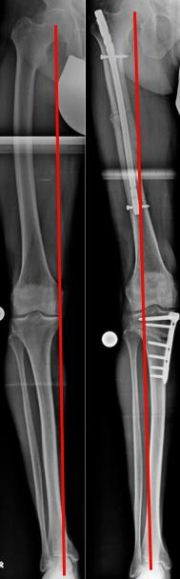

Zuklappende Osteotomie, kniegelenksnah, am Oberschenkel bei X-Bein (Bild 3).